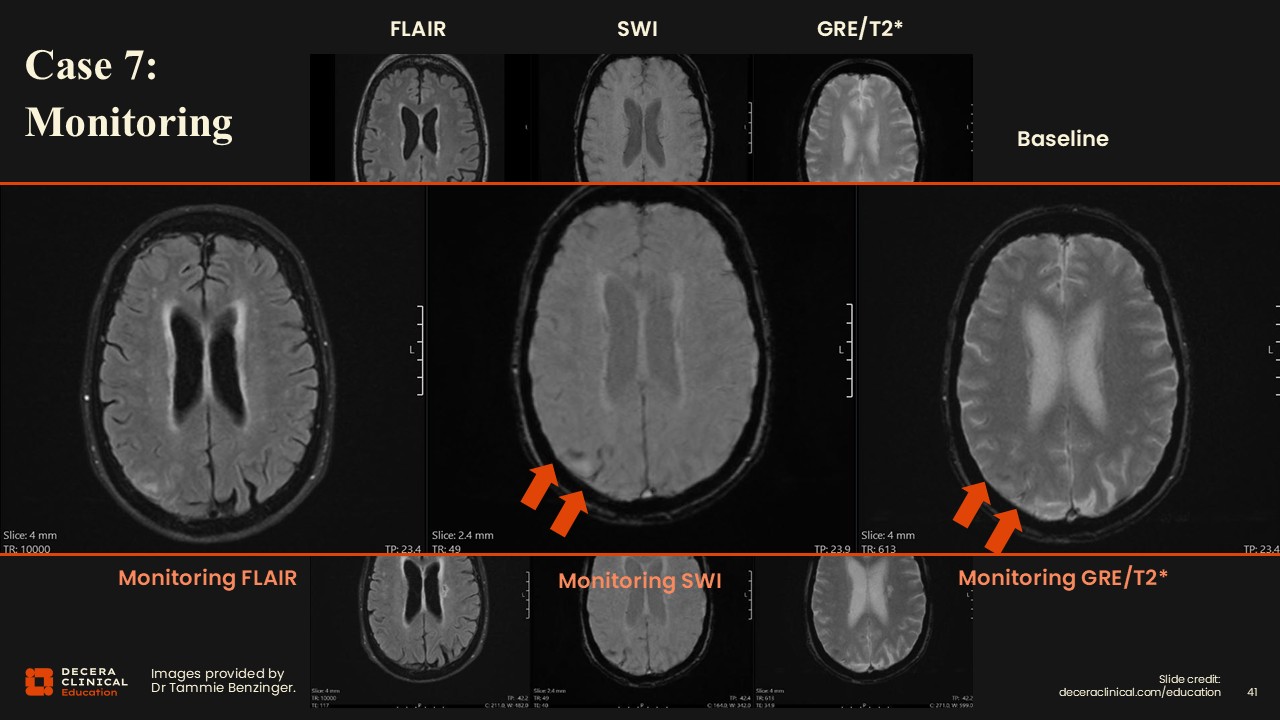

Case 7: ARIA Detection on Monitoring

Dr Benzinger:

For the final case, we have the same 3-visit setup: baseline, monitoring, and follow-up for a patient receiving ATT.

Case 7: ARIA Detection on Monitoring (Detail)

Upon inspection, vasogenic edema and sulcal effusions are noted on FLAIR, and then findings on SWI, and very subtle on the GRE/T2* as well.

Case 7: ARIA Detection on Monitoring (Grading)

Findings are consistent with mild ARIA-E and moderate ARIA-H with 2 siderosis.